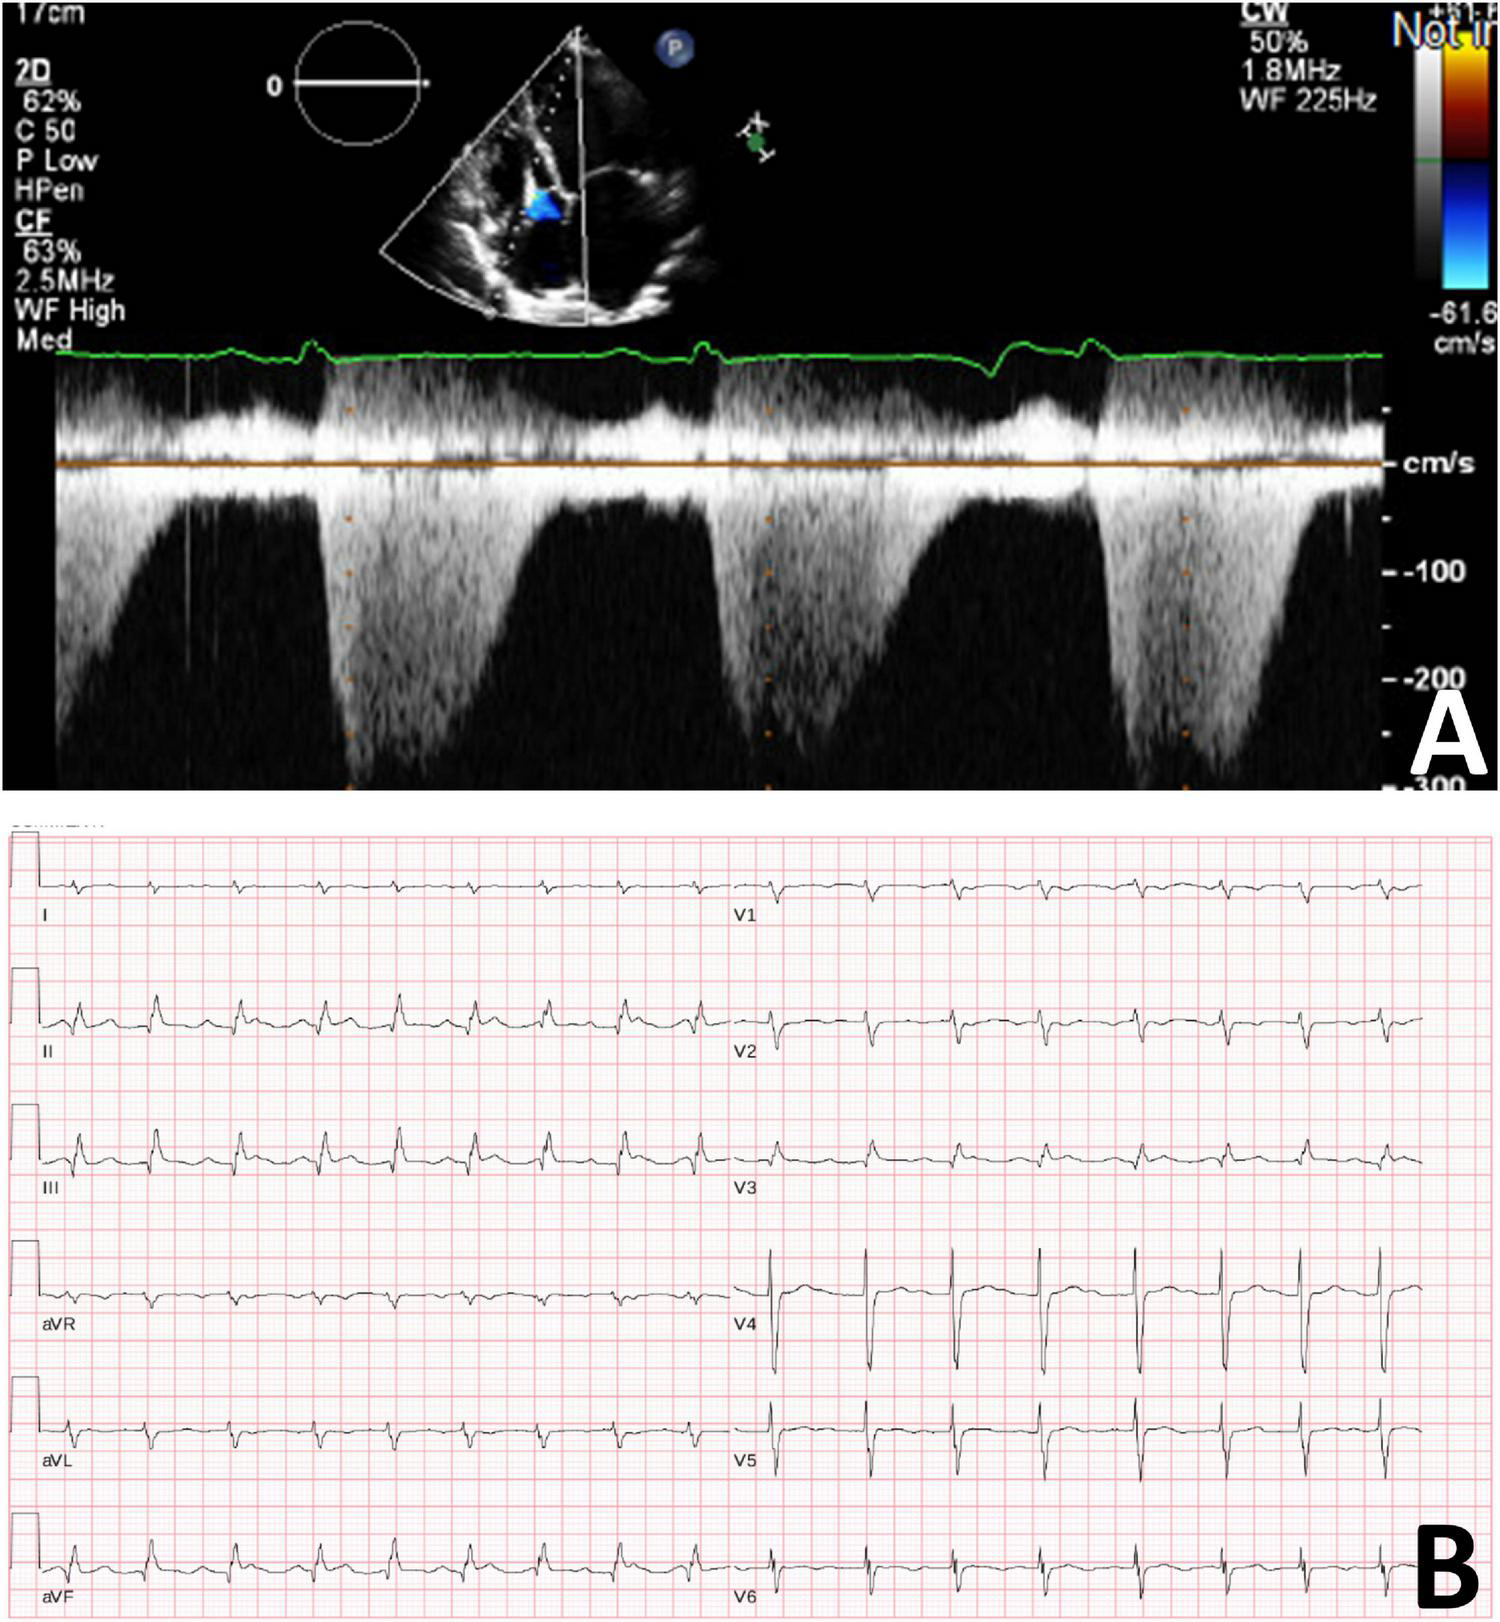

After several months, the patient discontinued her medications (aspirin, spironolactone, and perindopril), as she was concerned that these medications were causing abdominal pain. She acutely declined and she was readmitted to hospital with nausea, abdominal pain, orthopnea, and paroxysmal nocturnal dyspnea with a diagnosis of heart failure. Transthoracic echocardiogram demonstrated worsening cardiac function with severe global hypokinesis of the left ventricle, mild to moderately reduced right ventricular systolic function, severe functional mitral regurgitation, moderate tricuspid regurgitation and pericardial effusion (Figure 3). Given persistent severe low left ventricular ejection fraction, a dual chamber implantable cardioverter defibrillator was implanted for primary prevention. However, she deteriorated rapidly, developed further cardiogenic shock, and had multiple cardiac arrests with pulseless electrical activity. She required extracorporeal membrane oxygenation, cardiac support with a miniaturized ventricular assist pump/left ventricular assistive Impella device with anticoagulation, and renal replacement therapy. She had several complications including renal failure and septicemia and developed pneumonia with computerized tomography chest demonstrating confluent consolidation in the upper and lower lung lobes. Computerized tomography abdomen showed severe congestive hepatopathy and bowel ischemia. Unfortunately, she also developed multiple large epidural and subdural hematomas and cerebral edema with worsening neurological function. Care was withdrawn due to poor neurological and cardiac function with multiorgan failure. No autopsy was performed.

FIGURE 3

(A) Transthoracic cardiogram demonstrating severely reduced LV function with severe biatrial enlargement. (B) Electrocardiogram demonstrating sinus tachycardia with second degree A-V block (Mobitz 1).